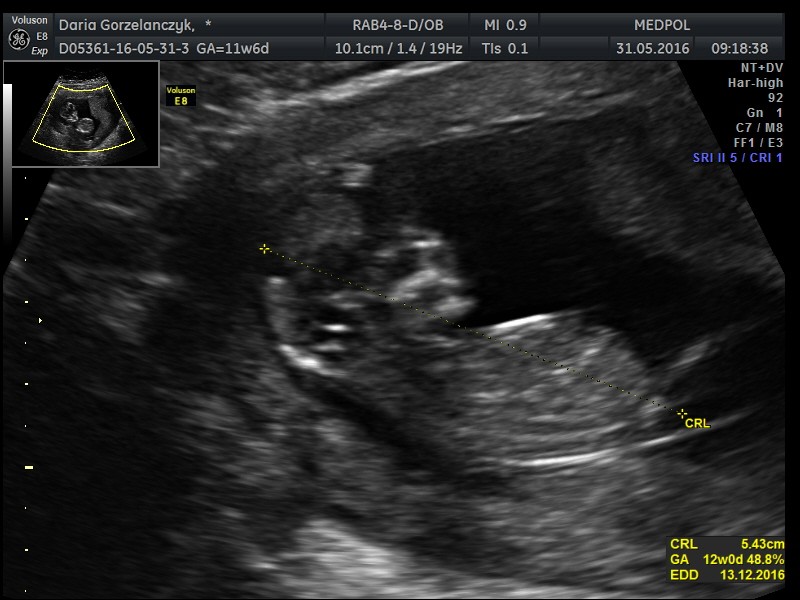

Dzięki Dziewczyny! Mam tych fot chyba z 30. Lekarz sie tak usmial z nub'owej teorii ale prawda jest taka,że ja pierwsza powiedzialam,że widzę damskiego nuba a on na koniec powiedział,że on widzi pipke a u nich w 95% się potwierdza :)))) bardzo fajna klinikę trafiłam i boskiego lekarza. Jestem przeszczesliwa [emoji134]

1466088164-1d1mld.jpeg

Napisane na GT-I9515 w aplikacji Forum BabyBoom